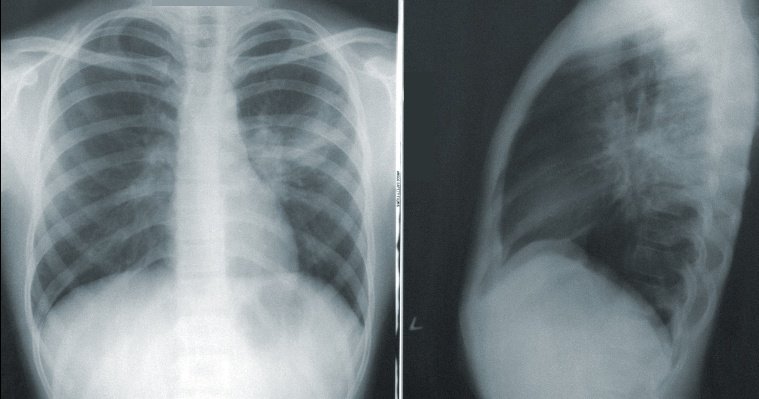

По данным за 10 месяцев текущего года, в регионе зафиксировано 4 166 случаев заболевания пневмонией, что на 17% ниже аналогичных показателей 2022 года.

Отмечается, что в целом в республике за последние 2 года заболеваемость снизилась более чем на 60%. Врачи считают, что это связано с появлением более «легких» штаммов коронавируса.

«В целом, при воспалении легких вирусная инфекция является проводником для бактериальной. Заболевание очень коварное — вирусно-бактериальная пневмония может привести к серьезной дыхательной недостаточности, вплоть до госпитализации в отделение реанимации и интенсивной терапии», — прокомментировала главный внештатный пульмонолог Минздрава Удмуртии Оксана Стародубцева.